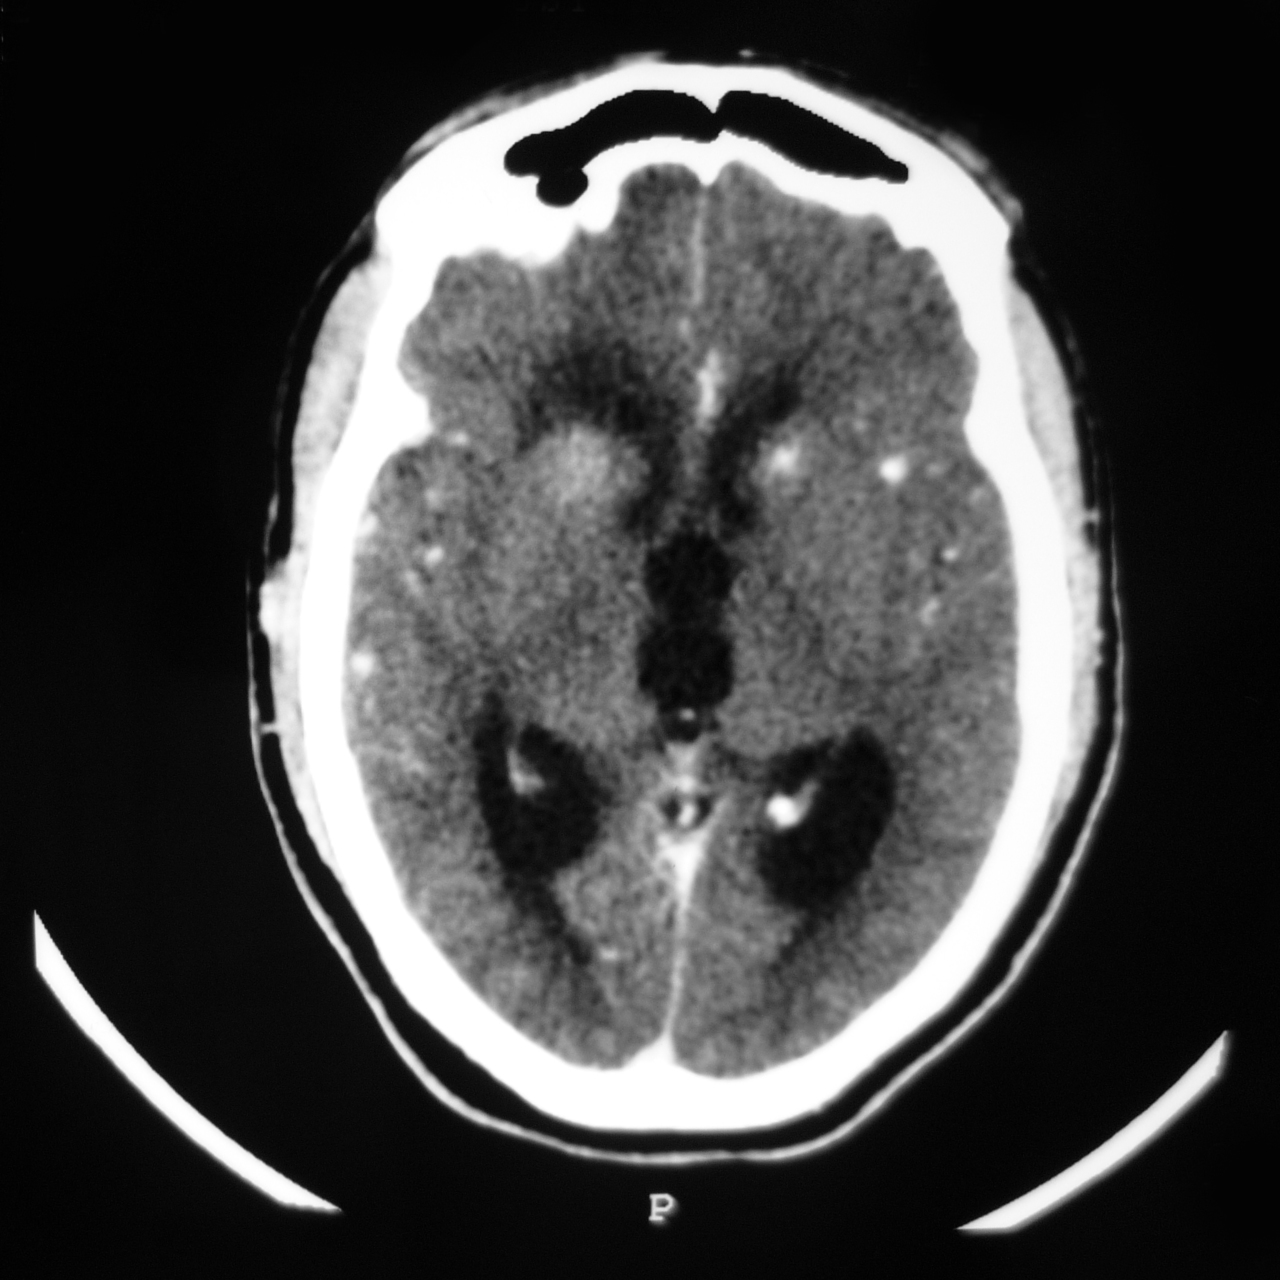

Quel est votre diagnostic ? Tuberculomes Post-artériographie cérébrale Métastases d'un cancer thyroïdien Cysticercose Il s'agit d'une cysticercose. Cryptococcose OK Valider mes réponses